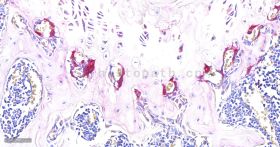

TRAP染色:TRAP 染色是用于检测骨组织、骨细胞中特征物质的染色,使破骨细胞呈红色,背景呈绿色或蓝色。抗酒石酸酸性磷酸酶(TRAP)为破骨细朐的标志酶,特异地分布于破骨细胞中,为破骨细胞所特有,通常作为鉴别破骨细胞的重要标志物。在含酒石酸的酸性条件下,TRAP 能将萘酚 AS-BI磷酸盐水解,产生的萘酚 AS-BI 立即与 fast red 或六偶氮副品红结合,在酶活性部位形成不溶性的红色染料,通过观察红色染料的形成可间接了解酸性磷酸酶的活性,进一步鉴别及分析破骨细胞的状态。

染色结果:破骨细胞呈红色,背景呈绿色或蓝色。